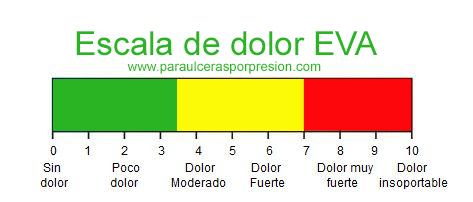

Dolor

En pacientes con insuficiencia arterial existen dos tipos característicos de dolor:5

- La claudicación intermitente. Una molestia o incapacidad asociada al ejercicio, la mas común es como un dolor tipo “calambre” en la pantorrilla , y que el reposo ayuda a aliviar rápidamente.

- El dolor isquémico en reposo. Suele aparecer como un dolor nocturno, insoportable para el paciente mas frecuente en la zona de los pies o cerca de una úlcera isquémica o dedo gangrenoso.

1.Úlceras por presión.Escala de EVA o escala del dolor utilizada en enfermería.[monografía en Internet].[acceso 30 de enero 2020]. Disponible en http://paraulcerasporpresion.com/cojines-antiescaras/escala-de-eva/